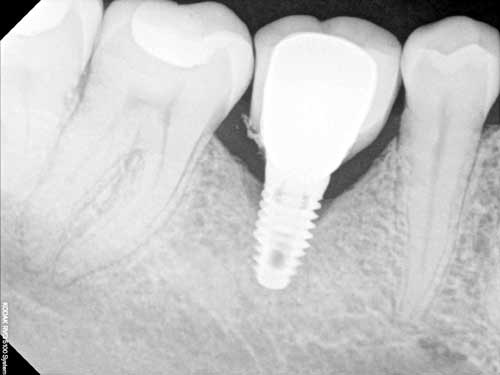

X-quang hỗ trợ bác sĩ khảo sát cấu trúc vùng hàm mặt mà mắt thường khó tiếp cận được. Kết hợp với thăm khám trong miệng, bác sĩ sẽ có cái nhìn toàn diện về các vấn đề răng hàm mặt.